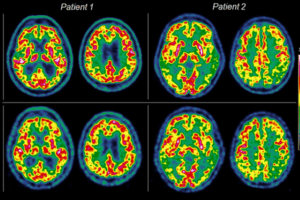

Enter the world of the PetVision Newsletter for a glimpse into an innovative project reshaping cancer diagnostic in the EU. Explore insights into the performance evaluation of panel detectors in…

In 2020, more than 2.7 million people were diagnosed with cancer in the European Union (EU), whereas 1.3 million people died from cancer. By 2035, the number of cancer cases…